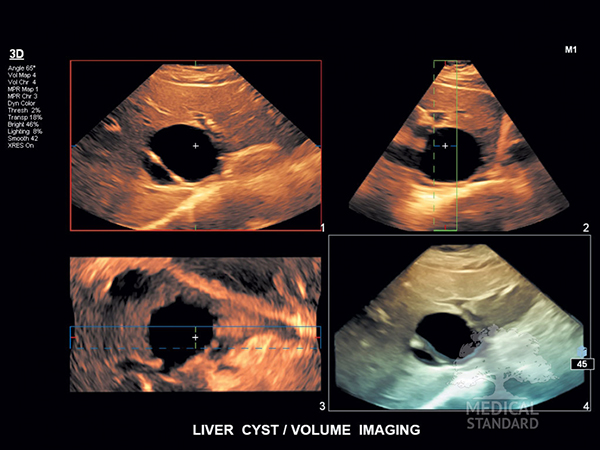

EPIQ 7 применяется при абдоминальных, кардиологических, объёмных исследованиях с использованием датчиков xMatrix, компрессионной эластографии и эластографии сдвиговой волны. Аппарат используется для диагностики малых, поверхностных органов, скелетно-мышечных тканей, сосудов, стресс эхокардиографии, визуализации кишечника, а также транскраниальной допплерографии, транспищеводной эхокардиографии и др.